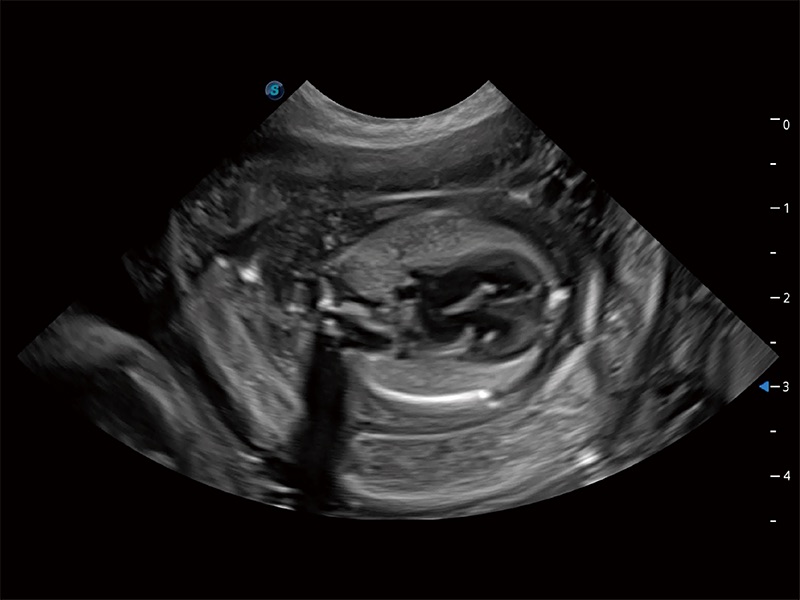

动物是人类最亲密的朋友和最值得信赖的伙伴。DB中国旗舰官方网站也一直致力于探索动物专用的超声影像解决方案。全新推出的ProPet系列,是DB中国旗舰官方网站在动物超声影像智能化、专业化、精准化的一次跨越式革新。动物不能用言语来表述自己的不适,通过超声影像,ProPet系列搭建了动物医生与不同物种沟通的“桥梁”,为动物医生注入了“治愈之力”。 ProPet 80 是DB中国旗舰官方网站匠心打造的一款高端动物专用彩超,采用性能卓越的全新硬件架构,极大提升超声系统的运行效率和数据处理能力,帮助动物医生从容应对日益增多的挑战性病例和日益多样化的临床需求。

高性能和先进的临床应用工具可以为动物医生提供临床信心。ProPet 80 搭载了先进的腹部和浅表应用工具,帮助医生在日常临床实践中发挥前所未有的作用。

ProPet 80 全新的动物超声智能软件和丰富的探头群,为动物医生提供了高清晰度和精细分辨率的图像,无论在宠物、马科、畜牧还是实验室动物等应用中都可以轻松应对,为您的日常工作带来满意的体验。